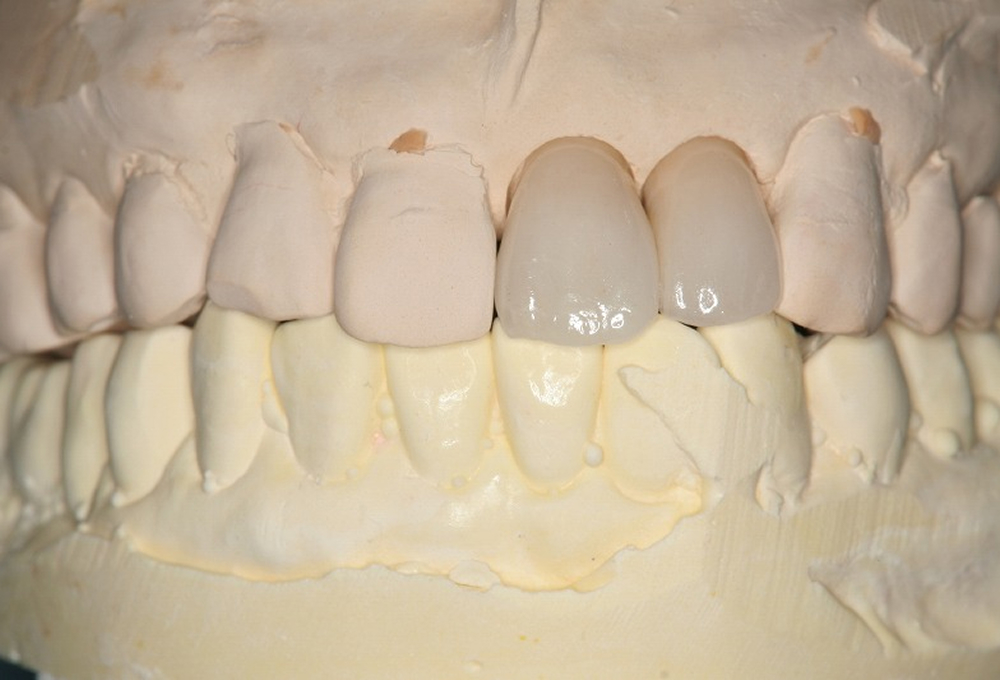

②診断用ワックス模型